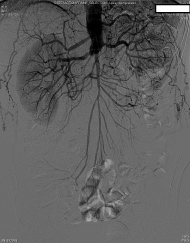

Preoperatively, the surgery service was queried by the anesthesiologist as to whether the routes of collateralization to the lower extremities were known. The response indicated that there had been intraabdominal collaterals demonstrated on angiography from the radial artery catheterization upon admission. The patient was then transported to the operating room, and a radial arterial line was placed during preoxygenation and prior to induction. After further consideration, the surgeon requested a delay of induction of anesthesia for further angiography review. Upon examination, a large right inferior epigastric artery was noted on the preoperative catheterization films, suggesting that collateral blood from the right internal mammary artery may supply the right lower extremity. The origin of collateral flow, however, could not be determined. Existing angiography was also unable to clearly demonstrate the collateral blood flow to the left lower extremity. At this point, the case was aborted before induction of anesthesia, and further angiography studies were ordered in consultation with a vascular surgeon. A subsequent aortogram and angiography of the internal mammary arteries demonstrated that collateral flow to the lower extremities was dependent on both the left and right internal mammary arteries (Figure 1, Figure 2 and Figure 3). Gastroepiploic artery was not considered as an alternative to the LIMA because of lack of institutional experience with the procedure.

Figure 2: Angiogram demonstrating collateral flow to the lower extremities from the internal mammary arteries via the inferior epigastric arteries.